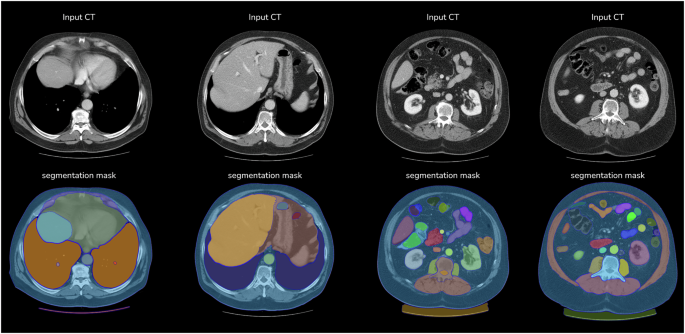

A detailed summary of model performance on the EBHI-SEG and Kvasir-SEG test sets is provided in Table 1. Grouping the models by architectural class enables an analysis of their evolutionary progression. Figures 1 and 2 shows the segmentation effect of our model in several cases.

Performance of PRISM-CRC model segmentation across colorectal histo-pathology subtypes.

Examples of PRISM-CRC model segmentation on diagnostic CT scans.